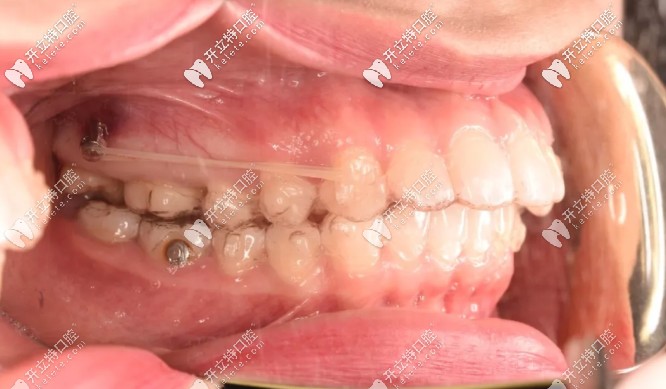

為了不拔牙,在設(shè)計(jì)方面時(shí)就溝通了打骨釘,我是在第18副的時(shí)候打的骨釘,看圖▼

術(shù)前把準(zhǔn)備好的布洛芬吃了,然后消毒打麻藥,到家后麻藥退了就是酸痛,異物感很重,頭兩天吃飯?zhí)赝纯?,還得注意清潔骨釘周?chē)?,以防食物卡住?/p>

完全恢復(fù)好之后,一點(diǎn)異物感都沒(méi)了!也米有不舒服的地方,就是得注意清潔,會(huì)有食物掛在骨釘那~